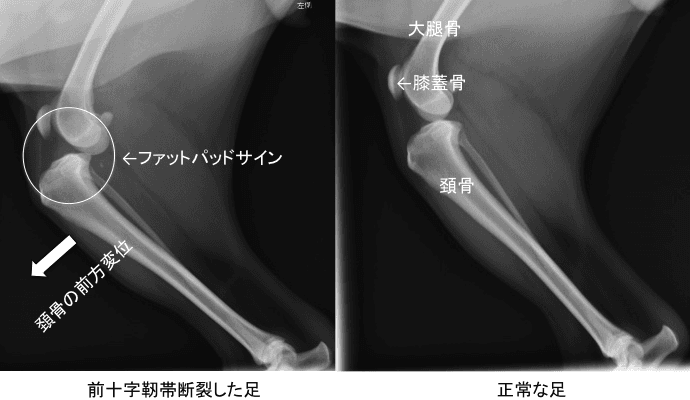

前十字靭帯は、膝の外側・後ろ側から内側・前側に向けて付着し、脛骨(すね)が前方向に滑らないようにストッパーとして機能しています。

そのため、前十字靭帯が切れるとストッパーがなくなり、脛骨が前方向に滑ってしまい、歩けなくなります。当然ですが切れたことによる痛みも非常に強いです。

ドロワーサイン(大腿骨と脛骨をもって、前後に滑るかどうか確認する検査)にて陽性反応が出れば、前十字靭帯の完全断裂で確定です。

ファットパッドサインという膝関節内の炎症を示唆する所見、またこのレントゲンでは脛骨が明らかに前方に滑っているため、ここまでくれば前十字靭帯の断裂が確定できます。